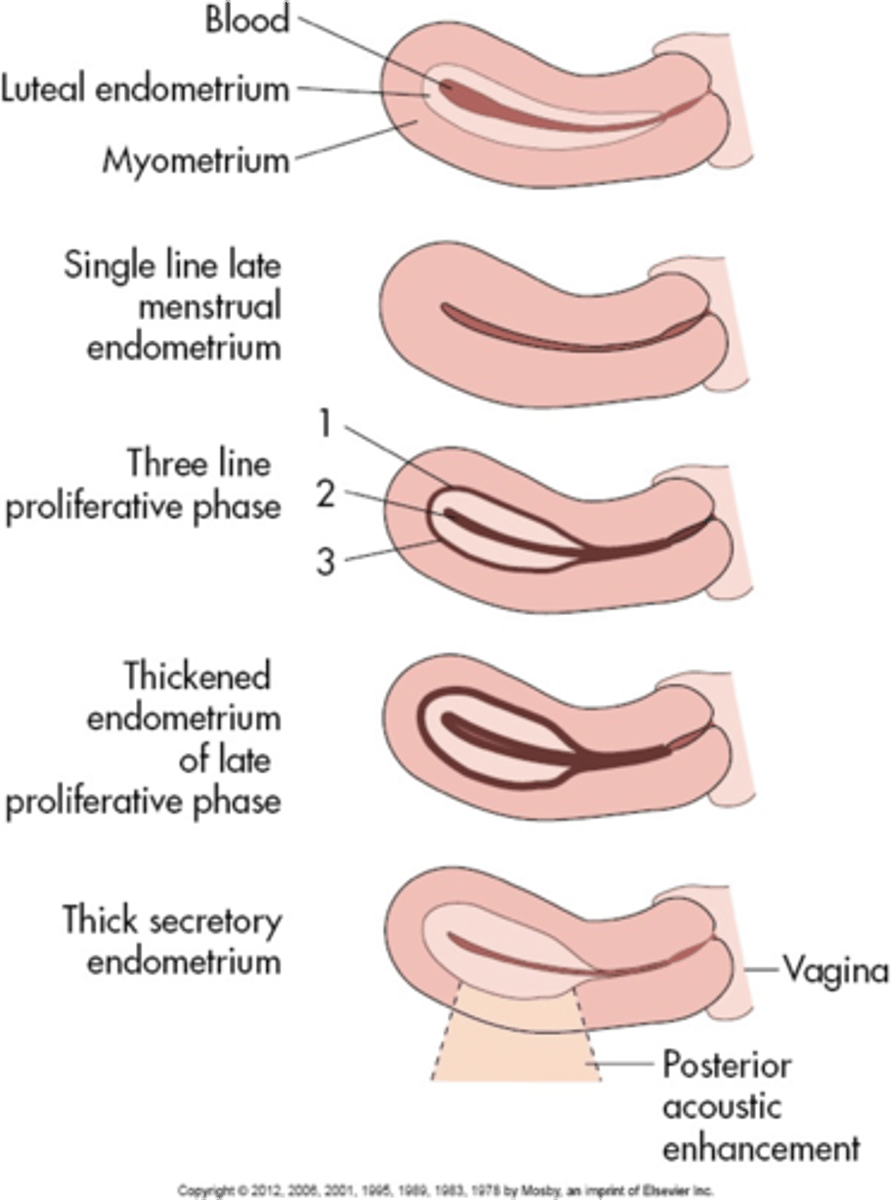

During the menstrual phase, the endometrium appears ___ and ___

thin; bright

During the early proliferative phase, the endometrium appears ___ and measures ___

bright; 4-8 mm

During the late proliferative phase, the ___ is visible and endometrium thickens to ___

3 line sign; 6-10 mm

During the secretory phase, the endometrium appears ___ and ___ and measures ___

thick; echogenic; 7-14 mm